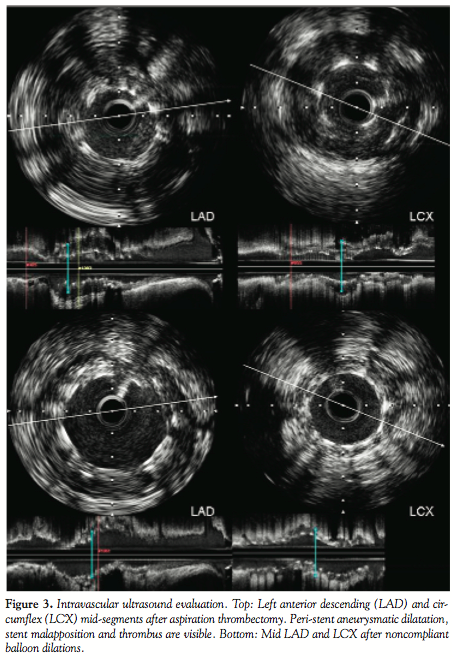

restored (TIMI 2 flow) (Figure 2). IVUS was performed. In the LAD, there was malapposition of the stent, with a large amount of thrombus detected and an image compatible with severe ectasia and a peri-stent coronary aneurysm [aneurysm cross-sectional area (CSA): 27.25 mm2; minimum lumen diameter (MLD): 1.6 mm; distal reference diameter (DR): 2.8 mm; and proximal reference diameter (PR): 3.5 mm]. The remaining vessel had non-significant fibrolipidic plaque and small calcification areas. In the LCX, thrombus was also evident and peri-stent dilation (aneurysm CSA: 20.36 mm2) with stent malapposition (similar to the LAD) was visible (MLD: 1.9 mm; DR: 2.6 mm; and PR: 2.75 mm) (Figure 3).

PCI was performed. Dilation of the LAD with 4 x 15 mm and 5 x 20 mm noncompliant balloons was conducted, followed by re-evaluation with IVUS. A flow-limiting dissection distal to the previous stent was detected and a 3.5 x 19 mm BMS (Titan 2 Cross Maxx, Hexacath, Paris, France) was deployed with distal overlapping. TIMI 3 flow was restored and no residual stenosis was present (MLD: 2.9 mm). The LCX was dilated with a 3 x 15 mm noncompliant balloon with a good final result (MLD: 2.5 mm) (Figure 4).